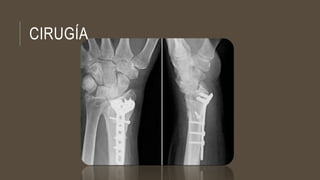

CIRUGÍA

Anestesia focal:

Inyección estrictamente aséptica de dimecaína o novocaína,

directamente en el foco de fractura radial y a nivel de la

apófisis estiloides cubital.

ANESTESIA